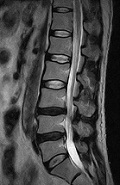

MRIは磁気共鳴画像とも呼ばれ、強い磁石と電波を使って、身体のあらゆる部位を撮影できる装置です。放射線を使用しないので被ばくの心配はなく、ラジオ波と同じ電波を利用して撮影しているため人体に優しい検査法です。 X線の画像と比べて筋肉・脊髄・内臓などが、明瞭かつ詳細に描出されます。MRIが有用なのは、脳梗塞・脳腫瘍などの脳疾患、動脈瘤などの血管障害、がん・子宮筋腫・椎間板ヘルニア・靭帯断裂など動きの小さい柔らかい組織での病変描出に適しています。 MRIの特性を利用して、造影剤を使わずに脳血管像(MRA) 胆管・膵管像(MRCP)の描出も可能です 。

実際の検査画像

| 頭部 | 頸椎 | 腰椎 | 腹部 |